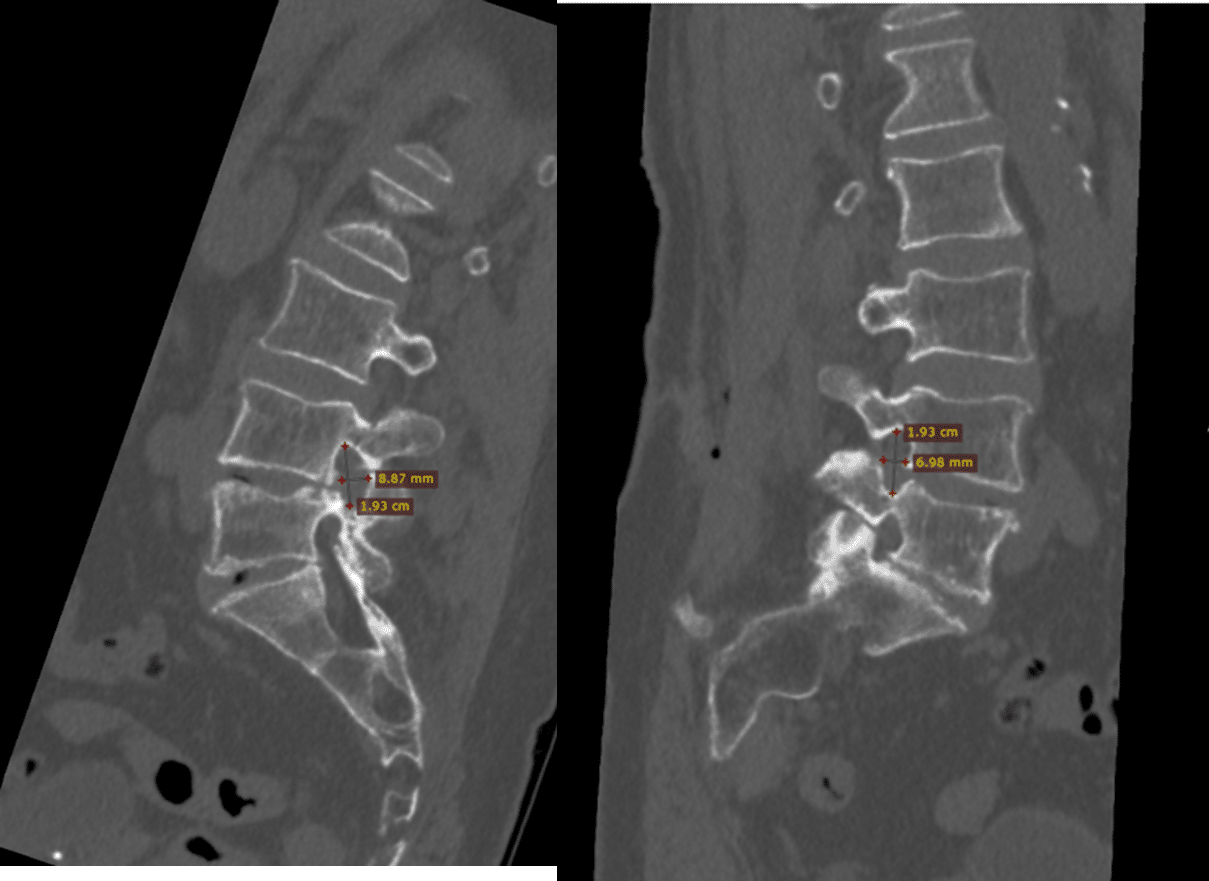

Obraz 2: TK Po Zabiegu

W badaniu tomografii komputerowej po zabiegu widoczne jest poszerzenie wymiarów kanału korzeniowego.

Obraz 3: Porównanie Otworów

W ocenie porównawczej otworów na poziomie segmentu L4/L5 potwierdziliśmy, że techniką endoskopową odtworzono wymiary otworu porównywalne do strony przeciwnej, która nie powodowała dolegliwości bólowych.